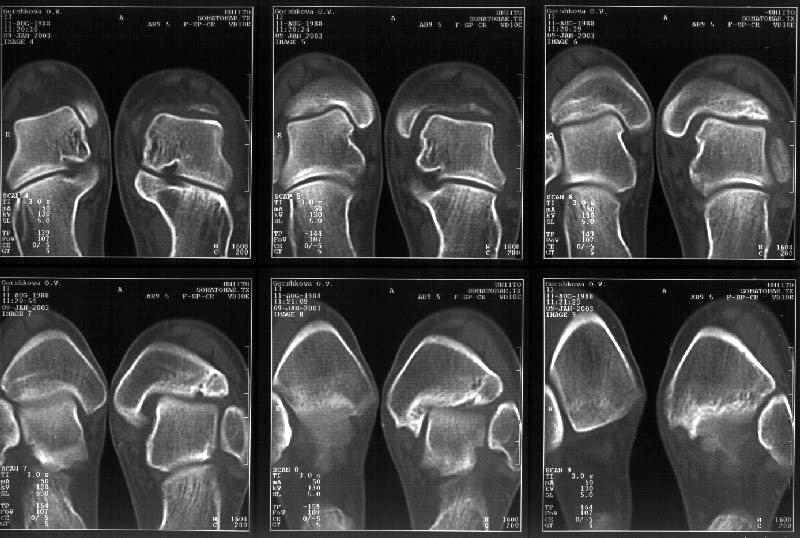

На следующий день пациентке сделали КТ. Может быть, после просмотра картинки будут другие предложения? Не убрать ли ве-таки этот фрагмент

позади внутренней лодыжки, который оттесняет таран кнаружи?

Здесь 4 среза, начиная от основания лодыжки и проксимальнее. Где, по Вашему мнению, проходит линия перелома, отделяющая переднюю часть внутренней лодыжки от большеберцовой кости? Заранее спасибо.

Сегодня пациентке сделали сравнительную КТ. А ксиальные и Фронтальные срезы приложены. Ваше мнение?

Фронтальные

Аксиальные